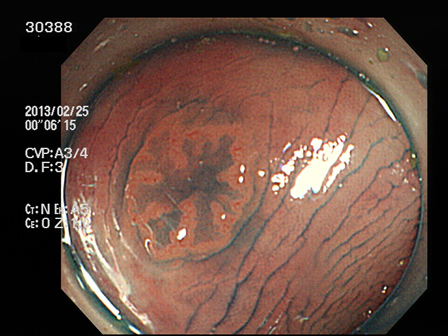

上記100名より抽出した平坦・陥凹型腺腫(=癌化の危険が高いが見落としやすい病変)の内視鏡写真

30388 30389 30391 30392 30394 30395 30396 30397 30399・・・・・・・の58名